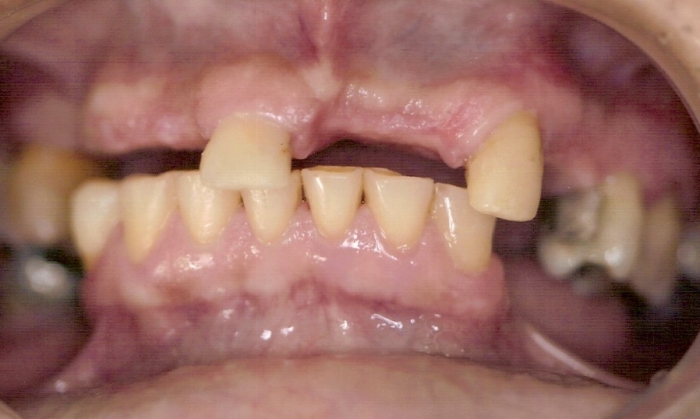

Imagem Inicial

Sorriso Inicial